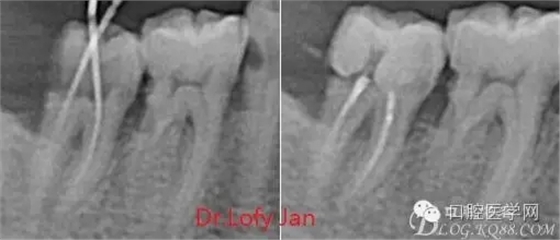

曲面斷層片在未試尖根管治療中的病例整理

前言:自己做的一些曲面斷層片在未試尖根管治療中的病例整理,發(fā)現(xiàn)問題很多包括自身的,技術(shù)的,還有設備的問題,予以總結(jié)整理并期待進一步提高。

根管治療術(shù)是牙體牙髓疾病治療中最復雜和最關(guān)鍵的治療項目。根管充填材料抵達根尖、并能嚴密堵塞根尖孔,是確保根管治療效果的關(guān)鍵指標。為了保證根管充填到位,醫(yī)生需要在術(shù)前照牙片以了解牙根根管的數(shù)量、彎曲程度和長度,在術(shù)中有時需要插針照牙片來精確測量根管長度,術(shù)后必須照牙片以確定是否根管充填到位,如果欠填或超填,就需要重新充填、重新照牙片確認,直到根管充填到位。所以,在患者接受根管治療時有時會反復照牙片。

病例分析:曲面斷層片在x線輔助診斷與檢查中目前大多數(shù)文獻和著作都建議只能作為初診拍片檢查手段,不能作為終末疾病的確診與手術(shù)療效的評價指標,臨床大部分中小型門診都因為設備不齊全導致信息偏差很大。